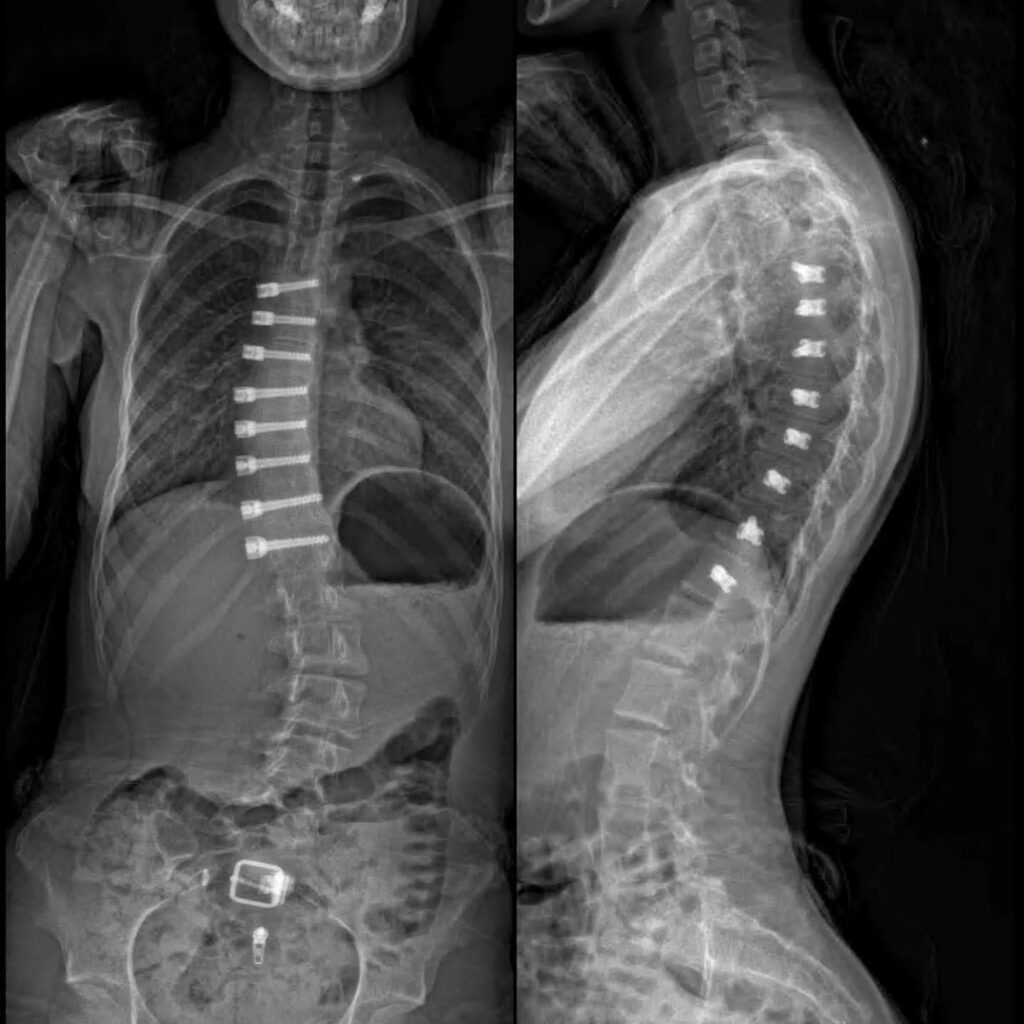

Tethering Surgery for Scoliosis

When scoliosis progresses to a point where non-surgical interventions are no longer effective, surgery becomes a critical consideration. While traditional fusion surgery has long been the standard, advancements in medical technology have introduced innovative alternatives. Among these, Tethering Surgery for Scoliosis has developed as a promising option, offering a unique approach to correcting spinal deformities. This technique aims to preserve spinal mobility and growth in younger patients, potentially leading to significant advantages over more rigid fusion procedures. By understanding the principles and benefits of tethering surgery, individuals and families can make more informed decisions about their scoliosis treatment journey.